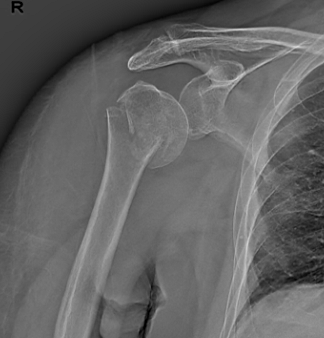

①术前肩关节X片

57岁的陈先生在骑电动车跌倒后摔伤了右肩关节 , 经检查 , 患者右侧肱骨近端粉碎性骨折 , 骨折累积范围较广 , 且多为体积小的碎骨块 , 门诊以“肱骨近端粉碎骨折”收治我院 。